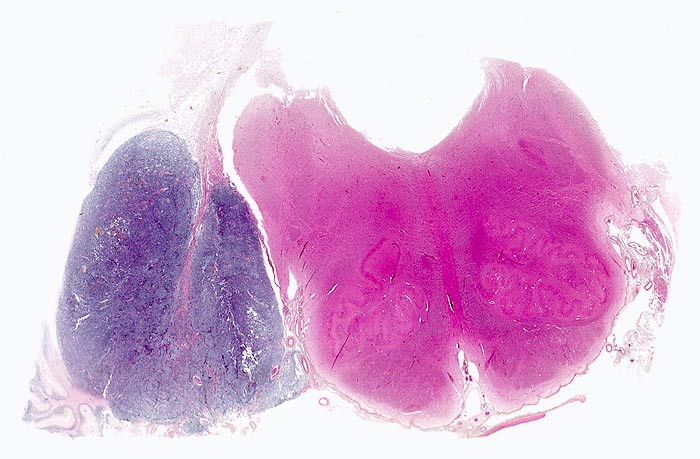

Die Makroskopie ist variabel. Meist sind Medulloblastome unscharf begrenzt, grau und weich, gelegentlich aber auch scharf begrenzt und derb.

• Scharf begrenzter rundlicher sehr zellreicher (deshalb blauer) Tumor.

Makroskopie

Virtuelles Präparat